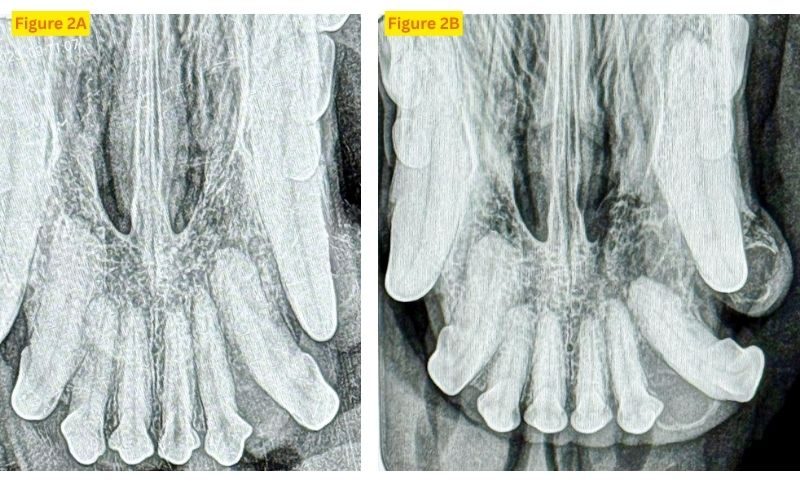

We recommended an incisional biopsy to determine what type of tumor Zoey had. Zoey was placed under general anesthesia, and full-mouth dental radiographs were obtained. Radiographs showed a mildly increased interdental space between 202 and 203 due to a soft tissue density and mild lysis at the alveolar margin (Figure 2). Soft tissue swelling was also noted lateral to tooth 204. Biopsies were obtained from the palatal portion of the mass and the buccal surface of 204. Histopathology returned as marked reactive mucosal hyperplasia with dysplasia and marked mixed inflammation.

Acanthomatous ameloblastoma is a very common odontogenic oral tumor in dogs. It represents up to 45 percent of all odontogenic tumors,3 but conventional ameloblastoma, also referred to as "solid/multicystic," "central," or "intraosseous" ameloblastoma, is a rare diagnosis. Both arise from cells responsible for the formation of the teeth, but acanthomatous ameloblastoma arises at the gingival margin, whereas conventional ameloblastoma arises deeper in the periodontium and can mimic a multilocular cyst. Though the radiographs taken at the time of the first biopsy showed no evidence of a cystic component, radiographs taken two months later showed at least two distinct cystic areas with a classic corticated rim of surrounding bone (Figures 2A and 2B).